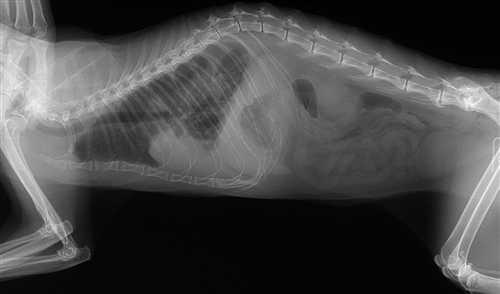

この症例は3歳のメス猫(避妊)です。

半年前からくしゃみ、鼻詰まりの症状があり1か月前から食べなくなったということでした。

貧血があり(Ht 13.5%)

血液を塗抹し顕微鏡で調べると赤血球にマイコプラズマらしきものが付着していました。

ニューキノロン系の抗生剤等を投与したところ3週間後にはHtが17%まで回復し

元気もよくなりました。